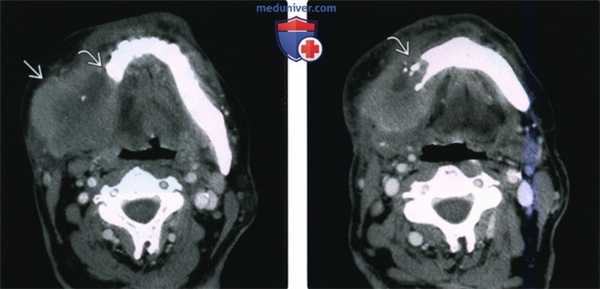

(Слева) На аксиальной КТ с КУ в жевательном пространстве справа визуализируется злокачественная фиброзная гистиоцитома нижней челюсти в виде минимально контрастирующегося солидного объемного образования, разрушающего ветвь и тело нижней челюсти. Жевательное пространство является известным местом возникновения сарком глубоких областей ли ца.

(Справа) На аксиальной КТ с КУ у этого же пациента визуализируется опухоль в жевательном пространстве справа, приводящая к обширной деструкции нижней челюсти. Обратите внимание на асимметрию лица на стороне поражения.2. КТ при саркоме жевательного пространства:

(Слева) КТ с КУ, аксиальная проекция. Злокачественная фиброзная гистиоцитома жевательного пространства и нижней челюсти. Солидная опухоль, которая умеренно накапливает контраст, располагается в правом жевательном пространстве и разрушает нижнюю челюсть, в том числе ее ветвь и тело. Жевательное пространство представляет собой глубокую область лица, в которой может возникать саркома.

(Справа) КТ с КУ, аксиальная проекция, тот же пациент. Солидная опухоль, умеренно накапливающая контраст, разрушает значительную часть нижней челюсти.2. КТ при саркоме жевательного пространства: